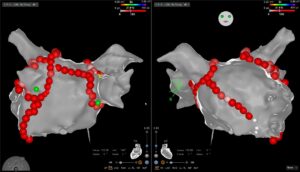

Eine bewährte Therapie bei verschiedensten Herzrhythmusstörungen, insbesondere wenn eine Rhythmuskontrolle erzielt werden soll, ist die Ablation mittels Spezialkatheter. Hierfür werden im Rahmen einer elektrophysiologischen Untersuchung (EPU) verschiedene Orte auf der Herzinnenseite, die für die Rhythmusstörungen verantwortlich sind, aufgesucht. Anschliessend wird die Elektrode des Katheters mit Hochfrequenzstrom erhitzt oder mittels Kälteabgabe angefroren. Die erzeugten Läsionen haben zum Ziel die Ausbreitung der elektrischen Impulse einzuschränken und somit die Rhythmusstörung zu eliminieren.

Eine bewährte Therapie bei verschiedensten Herzrhythmusstörungen, insbesondere wenn eine Rhythmuskontrolle erzielt werden soll, ist die Ablation mittels Spezialkatheter. Hierfür werden im Rahmen einer elektrophysiologischen Untersuchung (EPU) verschiedene Orte auf der Herzinnenseite, die für die Rhythmusstörungen verantwortlich sind, aufgesucht. Anschliessend wird die Elektrode des Katheters mit Hochfrequenzstrom erhitzt oder mittels Kälteabgabe angefroren. Die erzeugten Läsionen haben zum Ziel die Ausbreitung der elektrischen Impulse einzuschränken und somit die Rhythmusstörung zu eliminieren.

Typische Herzrhythmusstörungen, welche mittels Ablation behandelt werden können, sind:

- Vorhofflimmern (Abb 1 und 2)

Abbildungen:

Abb 1 und 2: Vorhofflimmern Ablation mit 3D-Mapping System

Eine bewährte Therapie bei verschiedensten Herzrhythmusstörungen, insbesondere wenn eine Rhythmuskontrolle erzielt werden soll, ist die Ablation mittels Spezialkatheter. Hierfür werden im Rahmen einer elektrophysiologischen Untersuchung (EPU) verschiedene Orte auf der Herzinnenseite, die für die Rhythmusstörungen verantwortlich sind, aufgesucht. Anschliessend wird die Elektrode des Katheters mit Hochfrequenzstrom erhitzt oder mittels Kälteabgabe angefroren. Die erzeugten Läsionen haben zum Ziel die Ausbreitung der elektrischen Impulse einzuschränken und somit die Rhythmusstörung zu eliminieren.

Typische Herzrhythmusstörungen, welche mittels Ablation behandelt werden können, sind:

- Vorhofflimmern (Abb 1 und 2)

Abbildungen:

Abb 1 und 2: Vorhofflimmern Ablation mit 3D-Mapping System